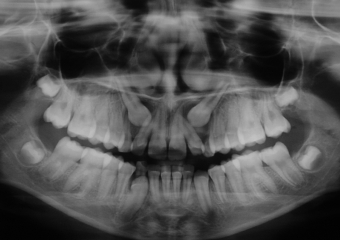

Rx Panorâmica inicial - 2014

Rx Panorâmica - 2018, com os caninos em posição